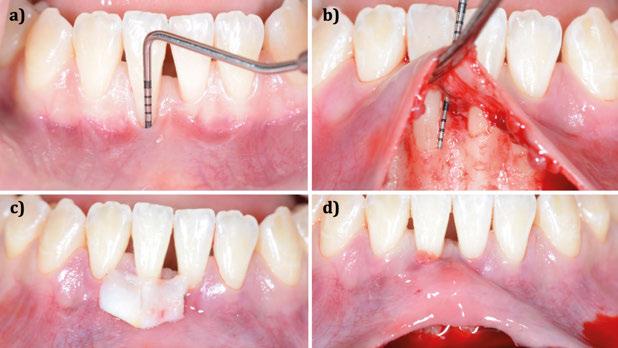

Figura 1. Caso clínico 1. Situación clínica basal de una paciente que presenta recesiones gingivales con pérdida de inserción interproximal en el quinto sextante. A la exploración se observa una profundidad de sondaje incompatible con salud en centro-vestibular del diente en posición de 41, presumiblemente combinado con una dehiscencia ósea.

CASO CLÍNICO 1 (FIGURAS 1-7)

Paciente de 32 años de edad que acude a la consulta preocupada por la situación de su diente en posición de 41. Le preocupa tanto a nivel de salud como a nivel estético. Además, refiere incapacidad para llevar a cabo un correcto cepillado de esa zona e hipersensibilidad dental.

A la exploración clínica presenta una recesión RT3 (23) en el diente en posición de 41. Además, carece de una banda de encía queratinizada adecuada (≥2mm) y presenta una reducción significativa de la

Figura 3. Intervención quirúrgica del caso clínico 1. a) situación clínica basal; b) colgajo de acceso apical vestibular y medición del defecto; c) posicionamiento ideal del injerto de tejido conectivo autólogo; d) sutura del injerto de tejido conectivo autólogo al colgajo a través del acceso apical vestibular.

Figura 4. Intervención quirúrgica del caso clínico 1. a) posición del injerto suturado a través del colgajo de acceso apical vestibular; b) utilización de aloinjerto particulado (OraGRAFT® Aloinjerto Cortical Particulado MIX 70% Mineralizado / 30% Desmineralizado) para rellenar el interior del defecto y cubrir la dehiscencia ósea; c) cobertura de la dehiscencia ósea con el aloinjerto particulado; d) customización de la lámina de cortical acorde a las características del defecto (Lámina de cortical desmineralizada Cortiflex® Salugraft Dental).

profundidad de vestíbulo combinada con la inserción alta y/o aberrante del frenillo labial incapacitando un correcto mantenimiento de la zona (24).

Se realiza una incisión biselada hacia coronal a espesor total en forma de parábola cóncava a apical en la mucosa labial con una hoja de bisturí no 10 alejada del fondo de vestíbulo actual. Es necesario destacar que la línea de incisión que estamos realizando se convertirá en el nuevo fondo de vestíbulo al final del procedimiento. El bisturí debe estar orientado a 45o al eje apico-coronal de los dientes. Además, la extensión mesio-distal de la incisión será acorde al número de recesiones adyacentes a tratar, debiendo extendernos idealmente un diente más a cada lado.

Una vez preparado el lecho receptor, dada la existencia de una situación combinada de recesión gingival y una dehiscencia ósea vestibular con pérdida de inserción interproximal, se opta por la utilización combinada de un injerto de tejido conectivo autólogo tuberositario, un sustituto de origen alogénico (Lámina de cortical desmineralizada Cortiflex® Salugraft Dental) que se fija mediante dos chinchetas a ambos lados, cubriendo un injerto óseo de origen alogénico particulado (OraGRAFT® Aloinjerto Cortical Particulado MIX 70% Mineralizado / 30% Desmineralizado). Primero se suturó el injerto de tejido conectivo autólogo al colgajo, después se colocaron las partículas